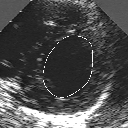

DETECTION AND TRACKING OF ANATOMICAL STRUCTURES USING DEFORMABLE TEMPLATES AND A NOISE MODEL ESTIMATION IN AN ECHOGRAPHIC SEQUENCE

In this work, we present a new method to shape-based segmentation of deformable anatomical structures in medical images and validate this approach by detecting and tracking the endocardial border in an echographic image sequence. To this end, a global prior knowledge of the endocardial contour is captured by a prototype template with a set of admissible deformations to take into account its inherent natural variability over time. In this approach, the data likelihood model rely on an accurate statistical modeling of the grey level distribution of each class present in the image. The parameters of this distribution mixture are given by a preliminary estimation step which takes into account the distribution shape of each class. Then the tracking problem is stated in a Bayesian framework where it ends up as an optimization problem. This one is then efficiently solved by a genetic algorithm combined with a steepest ascent procedure. This technique has been successfully applied on synthetic images and on a real echocardiographic image sequence. This method seems to be particularly well suited to handle ultrasound images with strong speckle noise on which edge information cannot be exploited. Finally, the local and global minimization procedure we propose is fast, robust and do not require initialization of the template close to the desired solution. Initialization may be defined at random, leading to segmentation and tracking procedure that are completely data driven. (slides)

Figure 1:   Tracking of the endocardial contour in a medical echographic sequence at different time frames during the cardiac cycle. From top left to bottom right : frame 1, 4, 6, 9, 12, 13, 18, 20, 27, 30, 35, 40, 41, 44, 46.